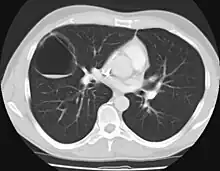

The earliest point at which a CPAM can be detected is by prenatal ultrasound. The classic description is of an echogenic lung mass that gradually disappears over subsequent ultrasounds. The disappearance is due to the malformation becoming filled with fluid over the course of the gestation, allowing the ultrasound waves to penetrate it more easily and rendering it invisible on sonographic imaging. When a CPAM is rapidly growing, either solid or with a dominant cyst, they have a higher incidence of developing venous outflow obstruction, cardiac failure and ultimately hydrops fetalis. If hydrops is not present, the fetus has a 95% chance of survival. When hydrops is present, risk of fetal demise is much greater without in utero surgery to correct the pathophysiology. The greatest period of growth is during the end of the second trimester, between 20 and 26 weeks.

A measure of mass volume divided by head circumference, termed cystic adenomatoid malformation volume ratio (CVR) has been developed to predict the risk of hydrops. The lung mass volume is determined using the formula (length × width × anteroposterior diameter ÷ 2), divided by head circumference. With a CVR greater than 1.6 being considered high risk. Fetuses with a CVR less than 1.6 and without a dominant cyst have less than a 3% risk of hydrops. After delivery, if the patient is symptomatic, resection is mandated. If the infant is asymptomatic, the need for resection is a subject of debate, though it is usually recommended. Development of recurrent infections, rhabdomyosarcoma, adenocarcinomas in situ within the lung malformation have been reported.[4]